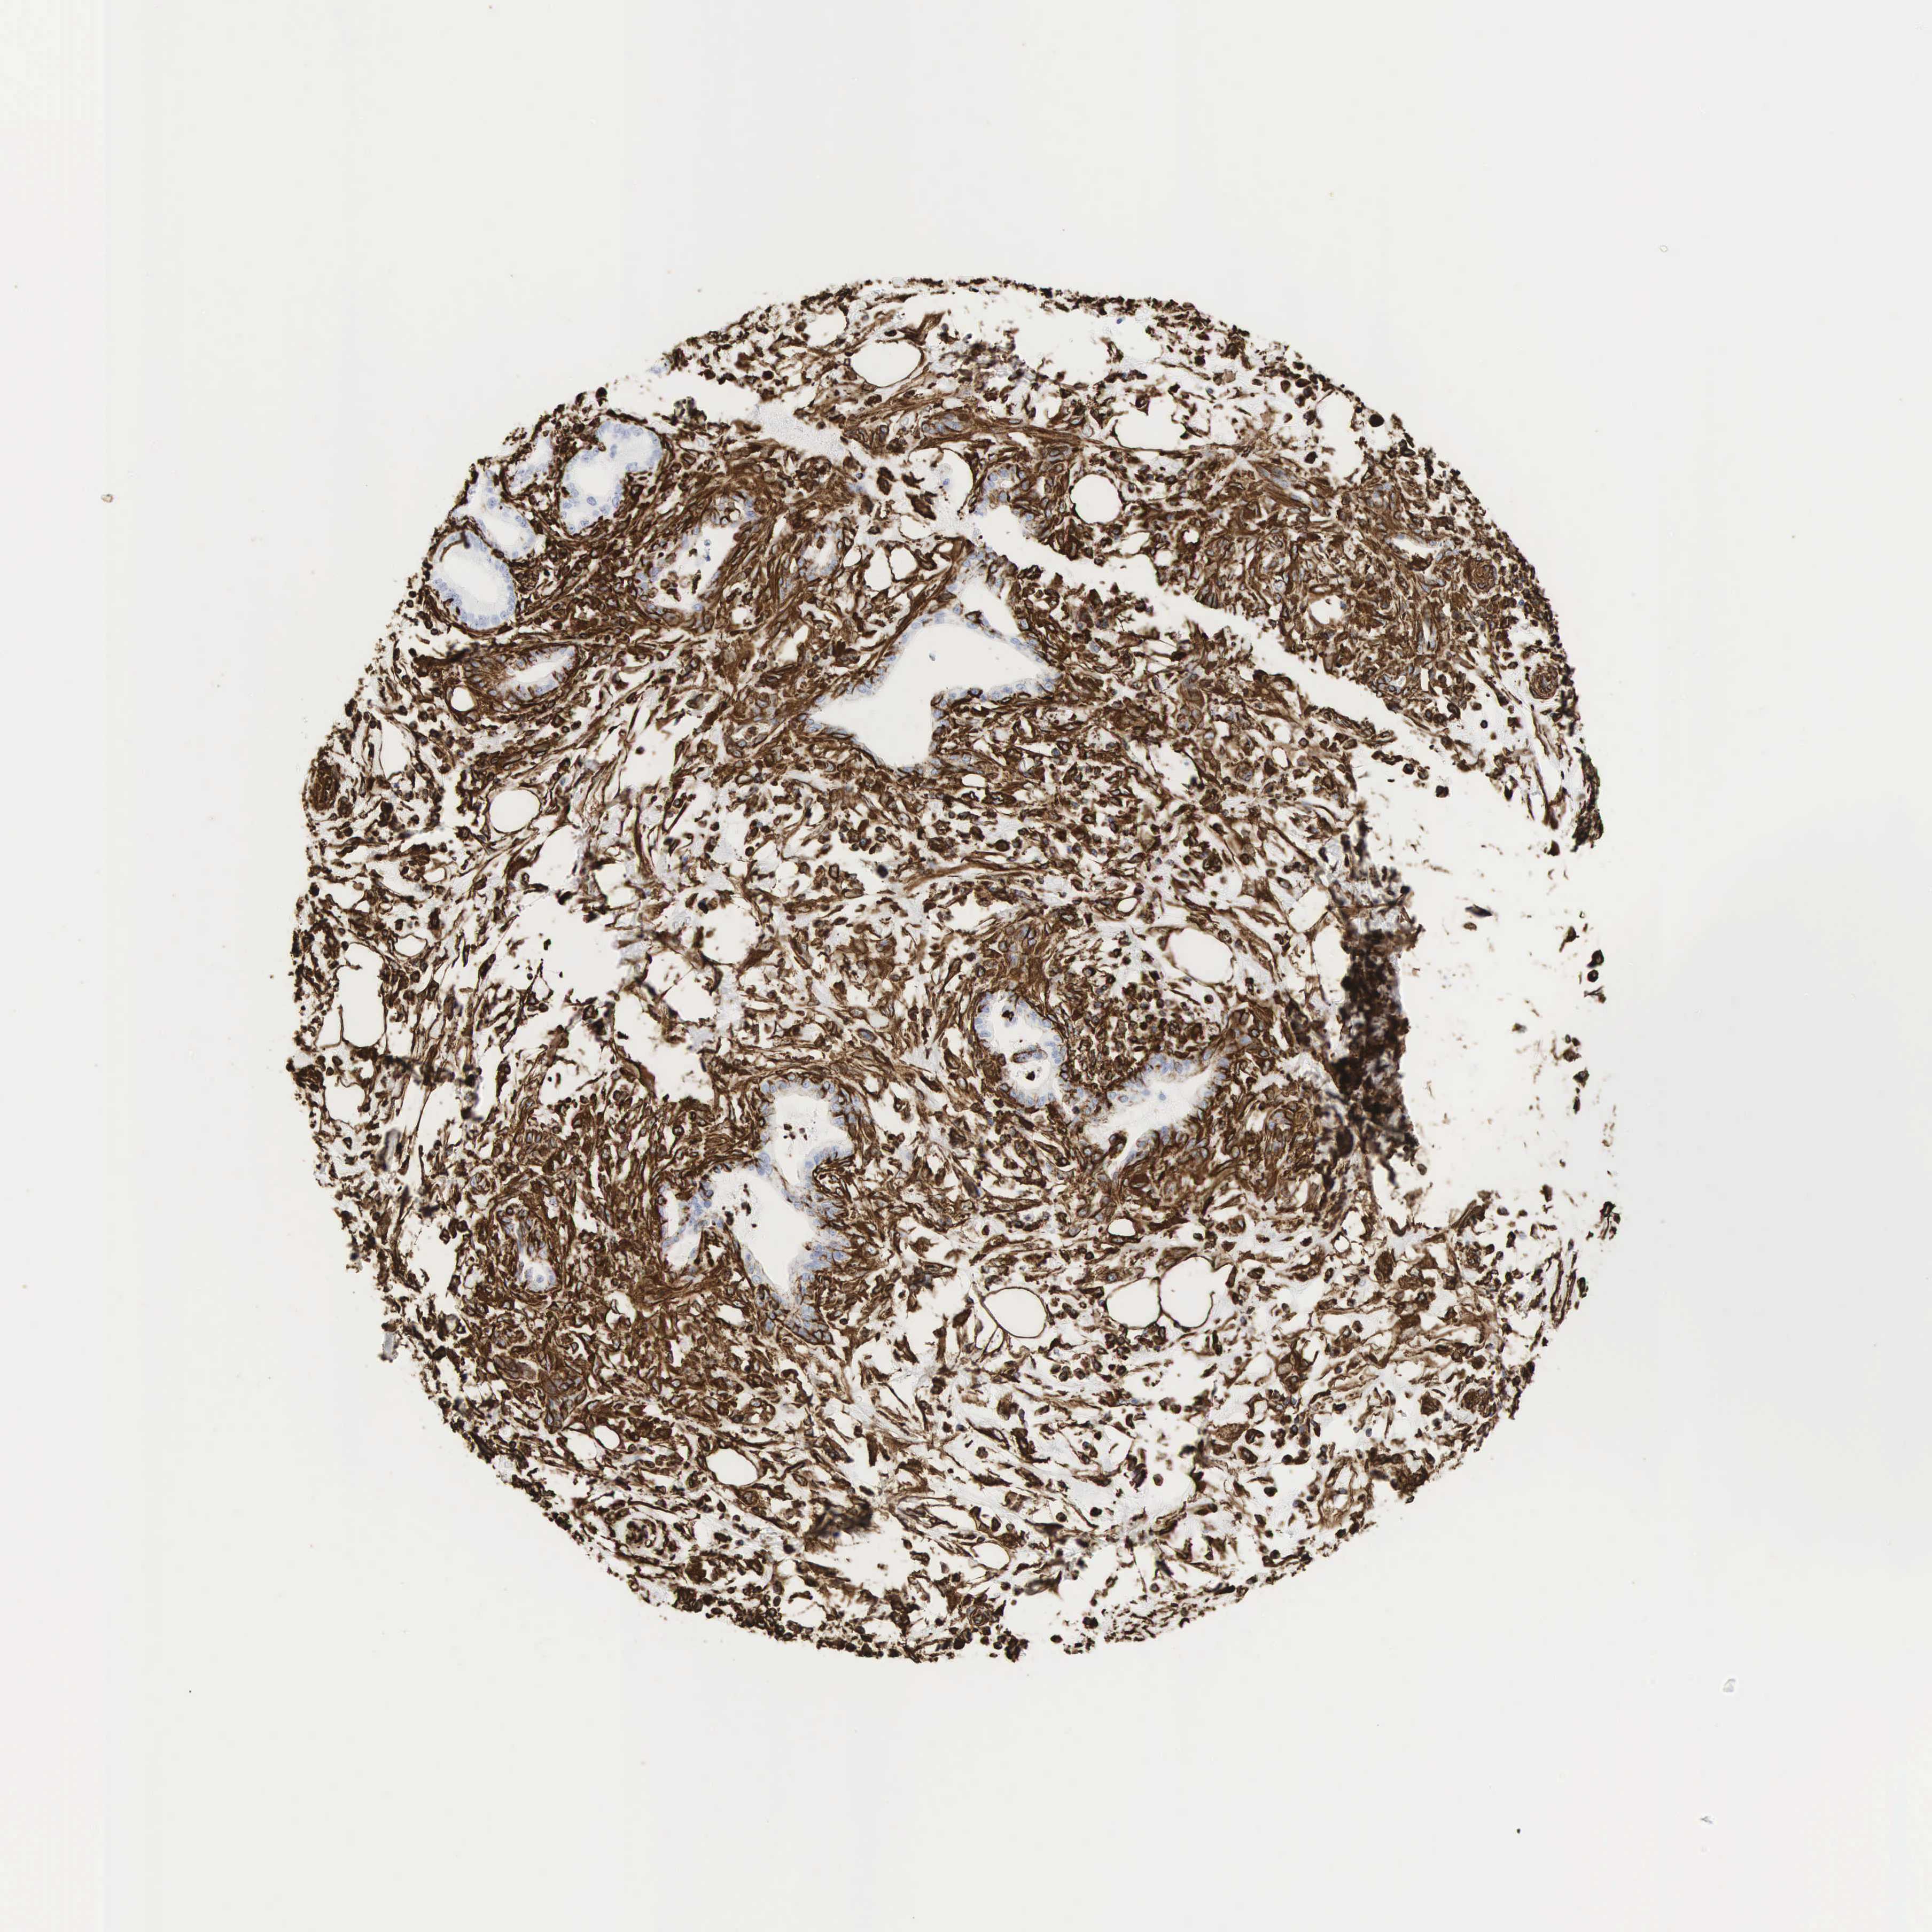

PANCREATIC CANCER - Protein expressioni

A mouse-over function shows sample information and annotation data. Click on an image to view it in a full screen mode. Samples can be filtered based on level of antibody staining by selecting one or several of the following categories: high, medium, low and not detected. The assay and annotation is described here.

Note that samples used for immunohistochemistry by the Human Protein Atlas do not correspond to samples in the TCGA dataset.

Antibody stainingi

Antibody staining in the annotated cell types in the current human tissue is reported as not detected, low, medium, or high, based on conventional immunohistochemistry profiling in selected tissues. This score is based on the combination of the staining intensity and fraction of stained cells.

Each image is clickable and will lead to virtual microscopy that enables deeper exploration of all samples and also displays staining intensity scores, fraction scores and subcellular localization as well as patient and tissue information for each sample.

Antibody HPA001762

Antibody CAB000080

Antibody CAB058687

Staining

High

Medium

Low

Not detected

Intensity

Strong

Moderate

Weak

Negative

Quantity

>75%

75%-25%

<25%

None

Location

Nuclear

Cytoplasmic/membranous

Cytoplasmic/membranous,nuclear

Adenocarcinoma, NOS

Adenocarcinoma, metastatic, NOS